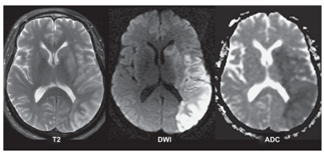

Observe a sequência de imagens Difusão, ADC e T2 em paciente

com Acidente Vascular Cerebral (AVC), adquiridas duas horas após

o evento.

A área afetada pelo AVC corresponde ao seguinte território vascular: